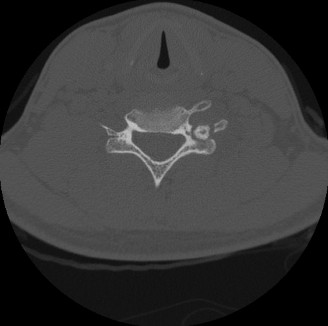

A 55-year-old female with a history of rheumatoid arthritis diagnosed at age 40 presents to your clinic compl…